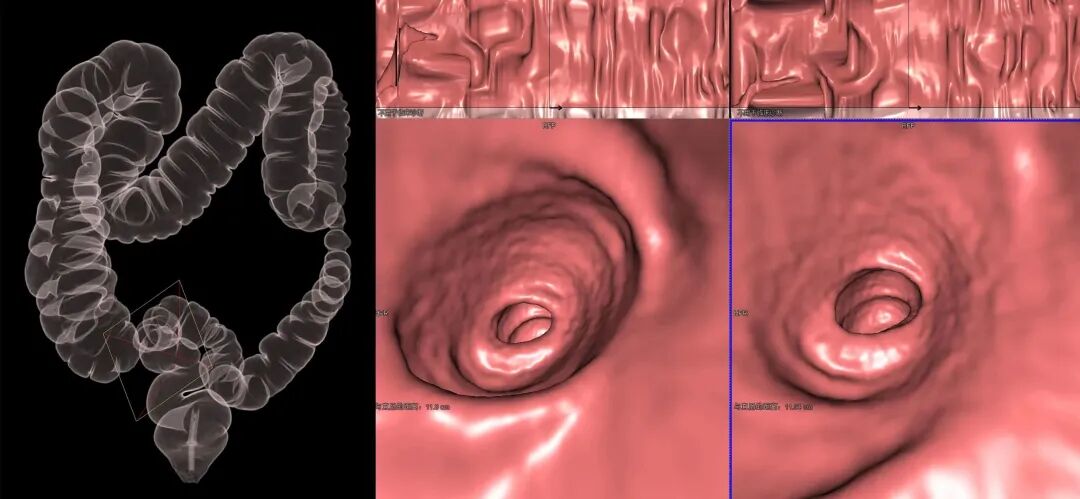

CT仿真结肠成像(CTC),也叫仿真结肠镜、虚拟结肠镜,是一种安全的、非侵入性的结肠检查方法。

简而言之就是向结肠内充气,以多层螺旋CT技术进行全结肠的仰卧位及俯卧位薄层扫描,通过影像处理后,生成类似于普通肠镜的检查图像。

CT仿真结肠镜图像